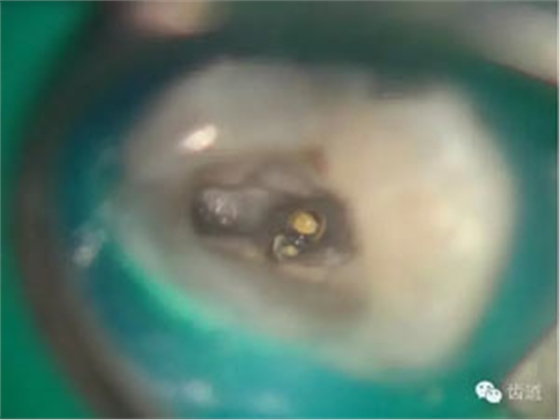

好的開(kāi)始就是成功的一半。通過(guò)CBCT了解根管的位置,形態(tài),方向。

檢查顯示:近頰及腭根充填恰填,遠(yuǎn)頰根管內(nèi)有少許充填物影像。根尖明顯低密度影像。

處理:顯微根管治療。放置橡皮障,去除暫封,顯微鏡下超聲去除頰側(cè)根管上段部分牙本質(zhì),探及遠(yuǎn)中根管口,見(jiàn)有糊劑遮蓋。Pathfile根管疏通,MTwo根管預(yù)備至2506#,配合3%次氯酸鈉和17%EDTA超聲蕩洗,干燥根管,放置氫氧化鈣糊劑,zoe暫封。